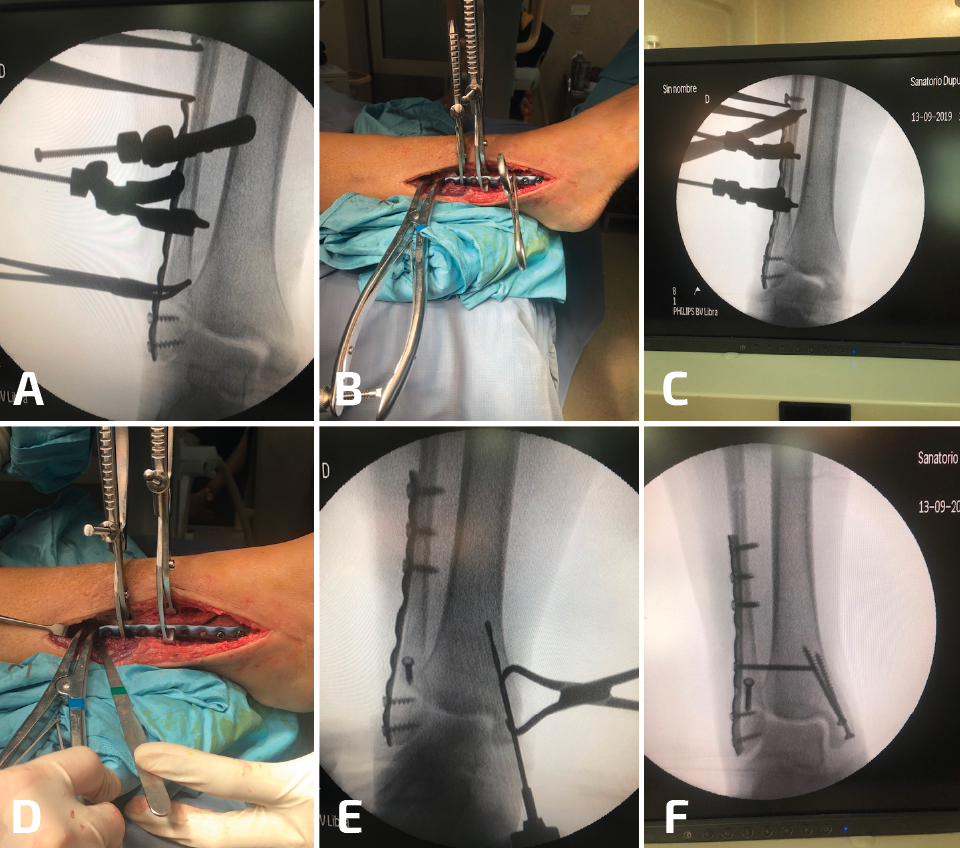

Durante la reconstrucción de la pseudoartrosis, es esencial realizar una artrotomía anterolateral para visualizar la reducción anatómica del peroné (Figura 1); sin embargo, el desbridamiento artroscópico de la articulación debe realizarse en forma simultánea no tanto para determinar el grado de artritis del tobillo, sino para tratar alguna lesión osteocondral no visible con la artrotomía anterolateral.

Figura 1. Cuando es necesaria una elongación significativa, se debe desbridar toda la sindesmosis anterior y dejar libre el peroné. Es indispensable para este paso un separador de láminas.

Figura 2. Aquí mostramos la técnica de elongación. Después del desbridamiento de la sindesmosis, se coloca la placa sobre el peroné y de colocan 2 o 3 tornillos distales (A, B). Se coloca un tornillo de 3,5 en el peroné proximal a la placa y el separador de láminas entre el tornillo y el borde proximal de la placa (C, D). En este caso, para corregir la consolidación viciosa del maléolo medial, se realizó una osteotomía (E) y el control de radioscopia intraoperatorio muestra una buena reducción de la sindesmosis (F).